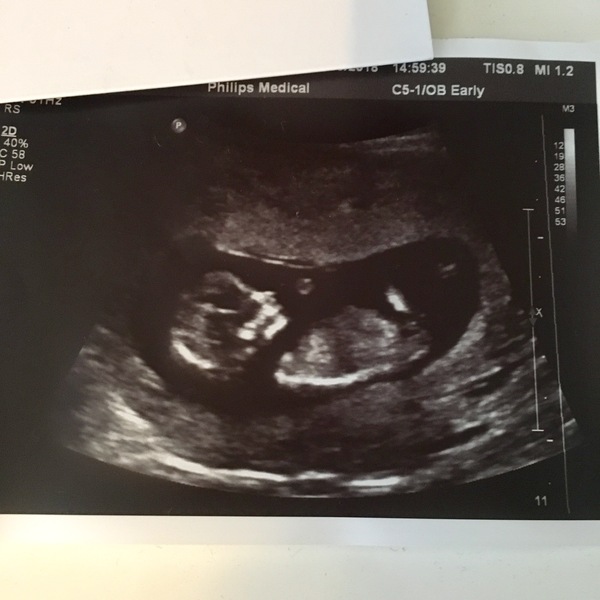

Here is mine. Measured at 12+5 which is only one day out from the early scan. It all feels very real now and I can feel myself relaxing a bit more.